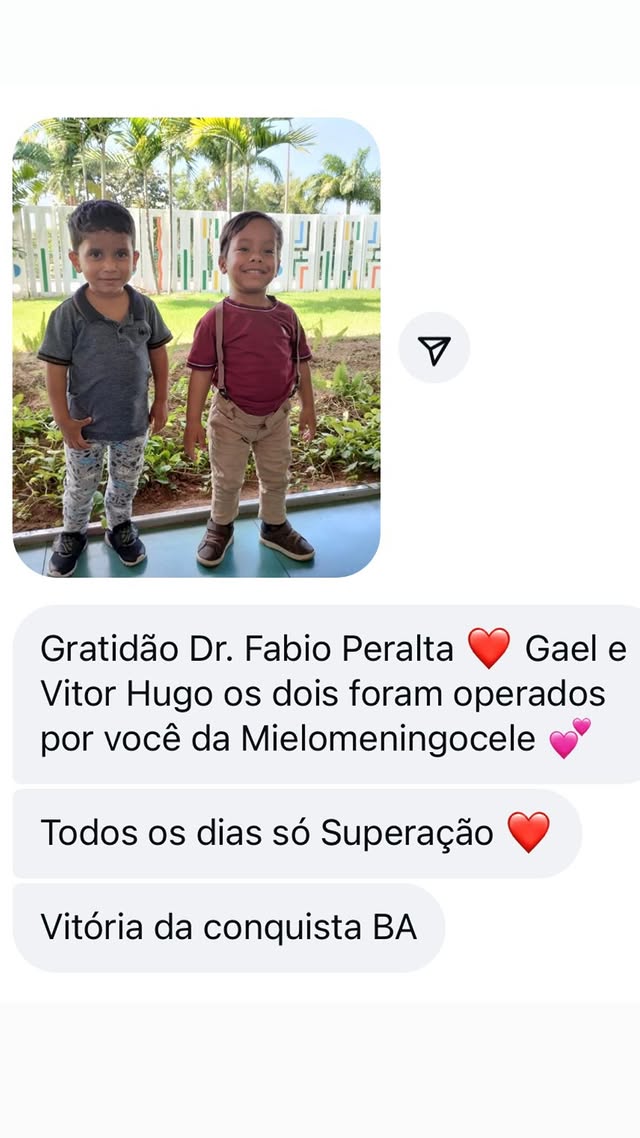

Sob o cuidado do Dr. Fábio Peralta, nosso Centro de Cirurgia Fetal acumula 2200+ cirurgias intrauterinas e a maior experiência mundial em correção da Mielomeningocele 800+.

Esperança viva: descubra o futuro

que a Valentina conquistou

"Valentina é a prova de que a força nasce junto com a vida. Hoje inspira todos ao seu redor com sua coragem. Sua trajetória mostra que, com apoio, fé e amor, é possível transformar desafios em conquistas. Essa é a história de uma menina que não se limitou ao diagnóstico, mas abraçou o futuro com esperança viva."